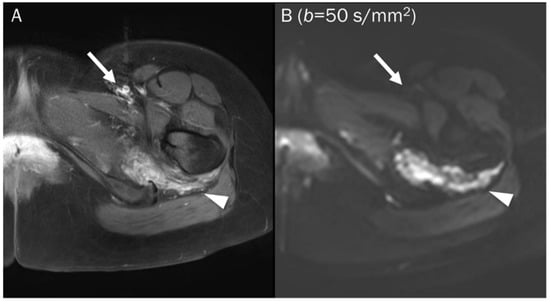

7.2. Hematoma

7.3. Benign Bone and Soft Tissue Tumors